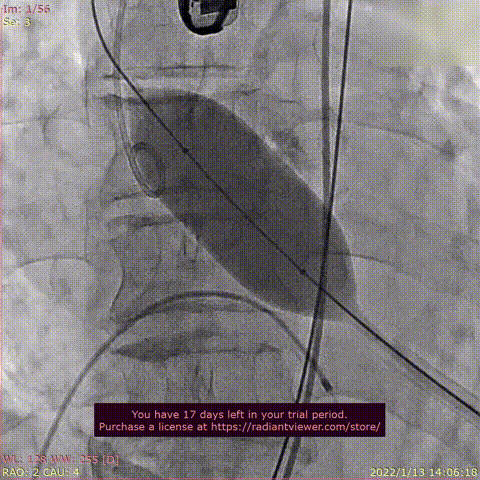

术前DSA造影